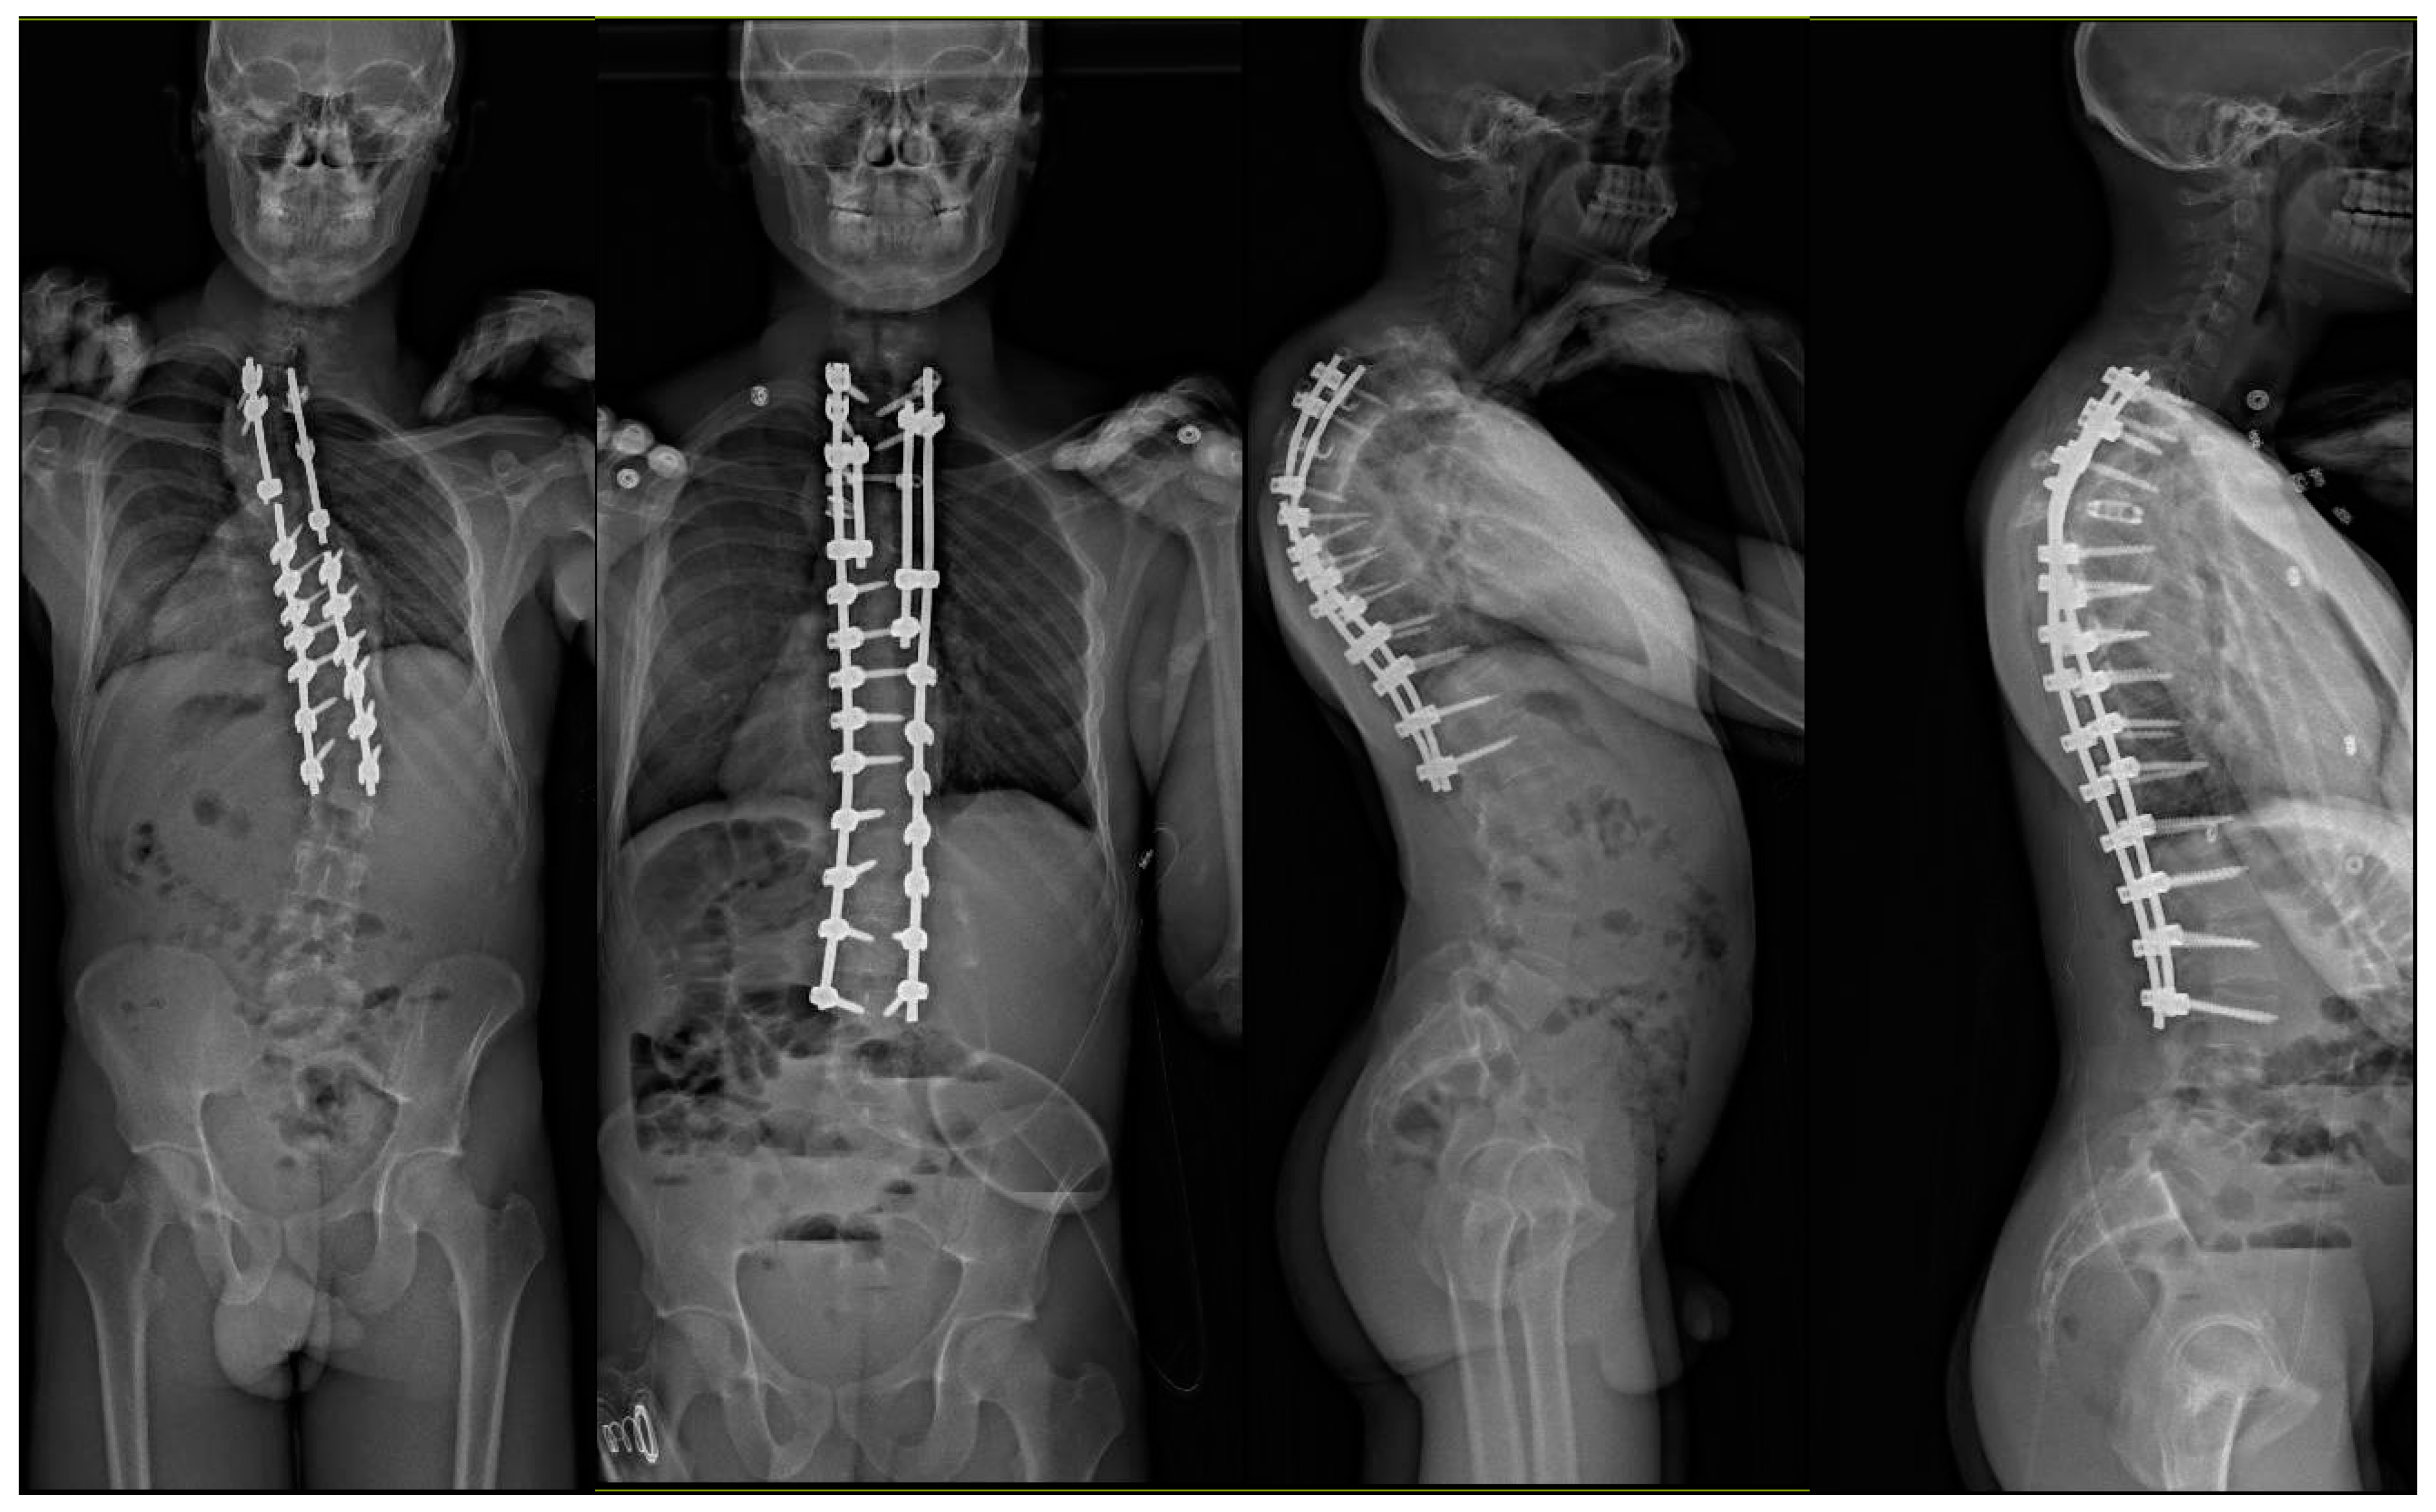

2. Case Discussions